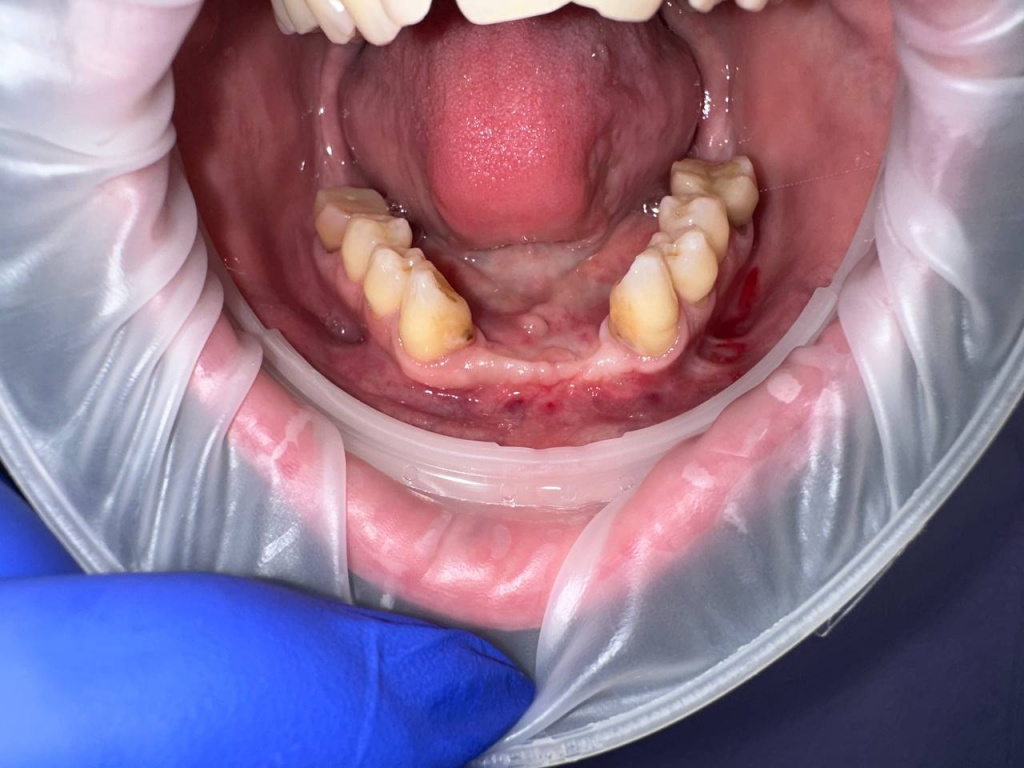

Уже много лет использую в своей практике имплантаты IMPRO. В этот раз мне предоставили линейку IMPRO Respect нового дизайна с широкими лепестками резьбы по отношению к телу имплантата. За счет чего получилось установить имплантаты в переднем отделе в узком гребне и с плохим костным предложением пациента. Ни разу не сталкивалась с осложнениями или проблем с имплантатми IMPRO Implantem. В этот раз не было исключением, была проведена операция через навигационный шаблон, имплантаты стабилизировались с хорошим торком. Хирургический набор и протоколы достаточно просты и удобны. Будем ждать ортопедической части, спустя месяц имплантаты стоят хорошо!

Пациент — мужчина 54 года.